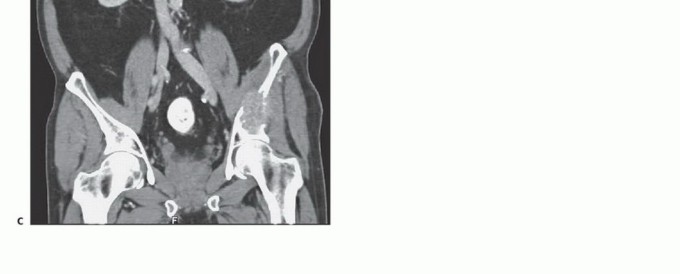

- التصوير المقطعي المحوسب (CT Scan): يوفر صورًا مقطعية مفصلة للعظام والأنسجة الرخوة، ويساعد في تحديد حجم الورم، مدى انتشاره داخل العظم، وعلاقته بالهياكل المحيطة.

- التصوير بالرنين المغناطيسي (MRI): يُعد الأداة الأكثر حساسية لتقييم الأنسجة الرخوة ونخاع العظم، ويكشف عن النقائل في مراحلها المبكرة، ويحدد مدى انتشار الورم في القناة الشوكية أو الأعصاب.